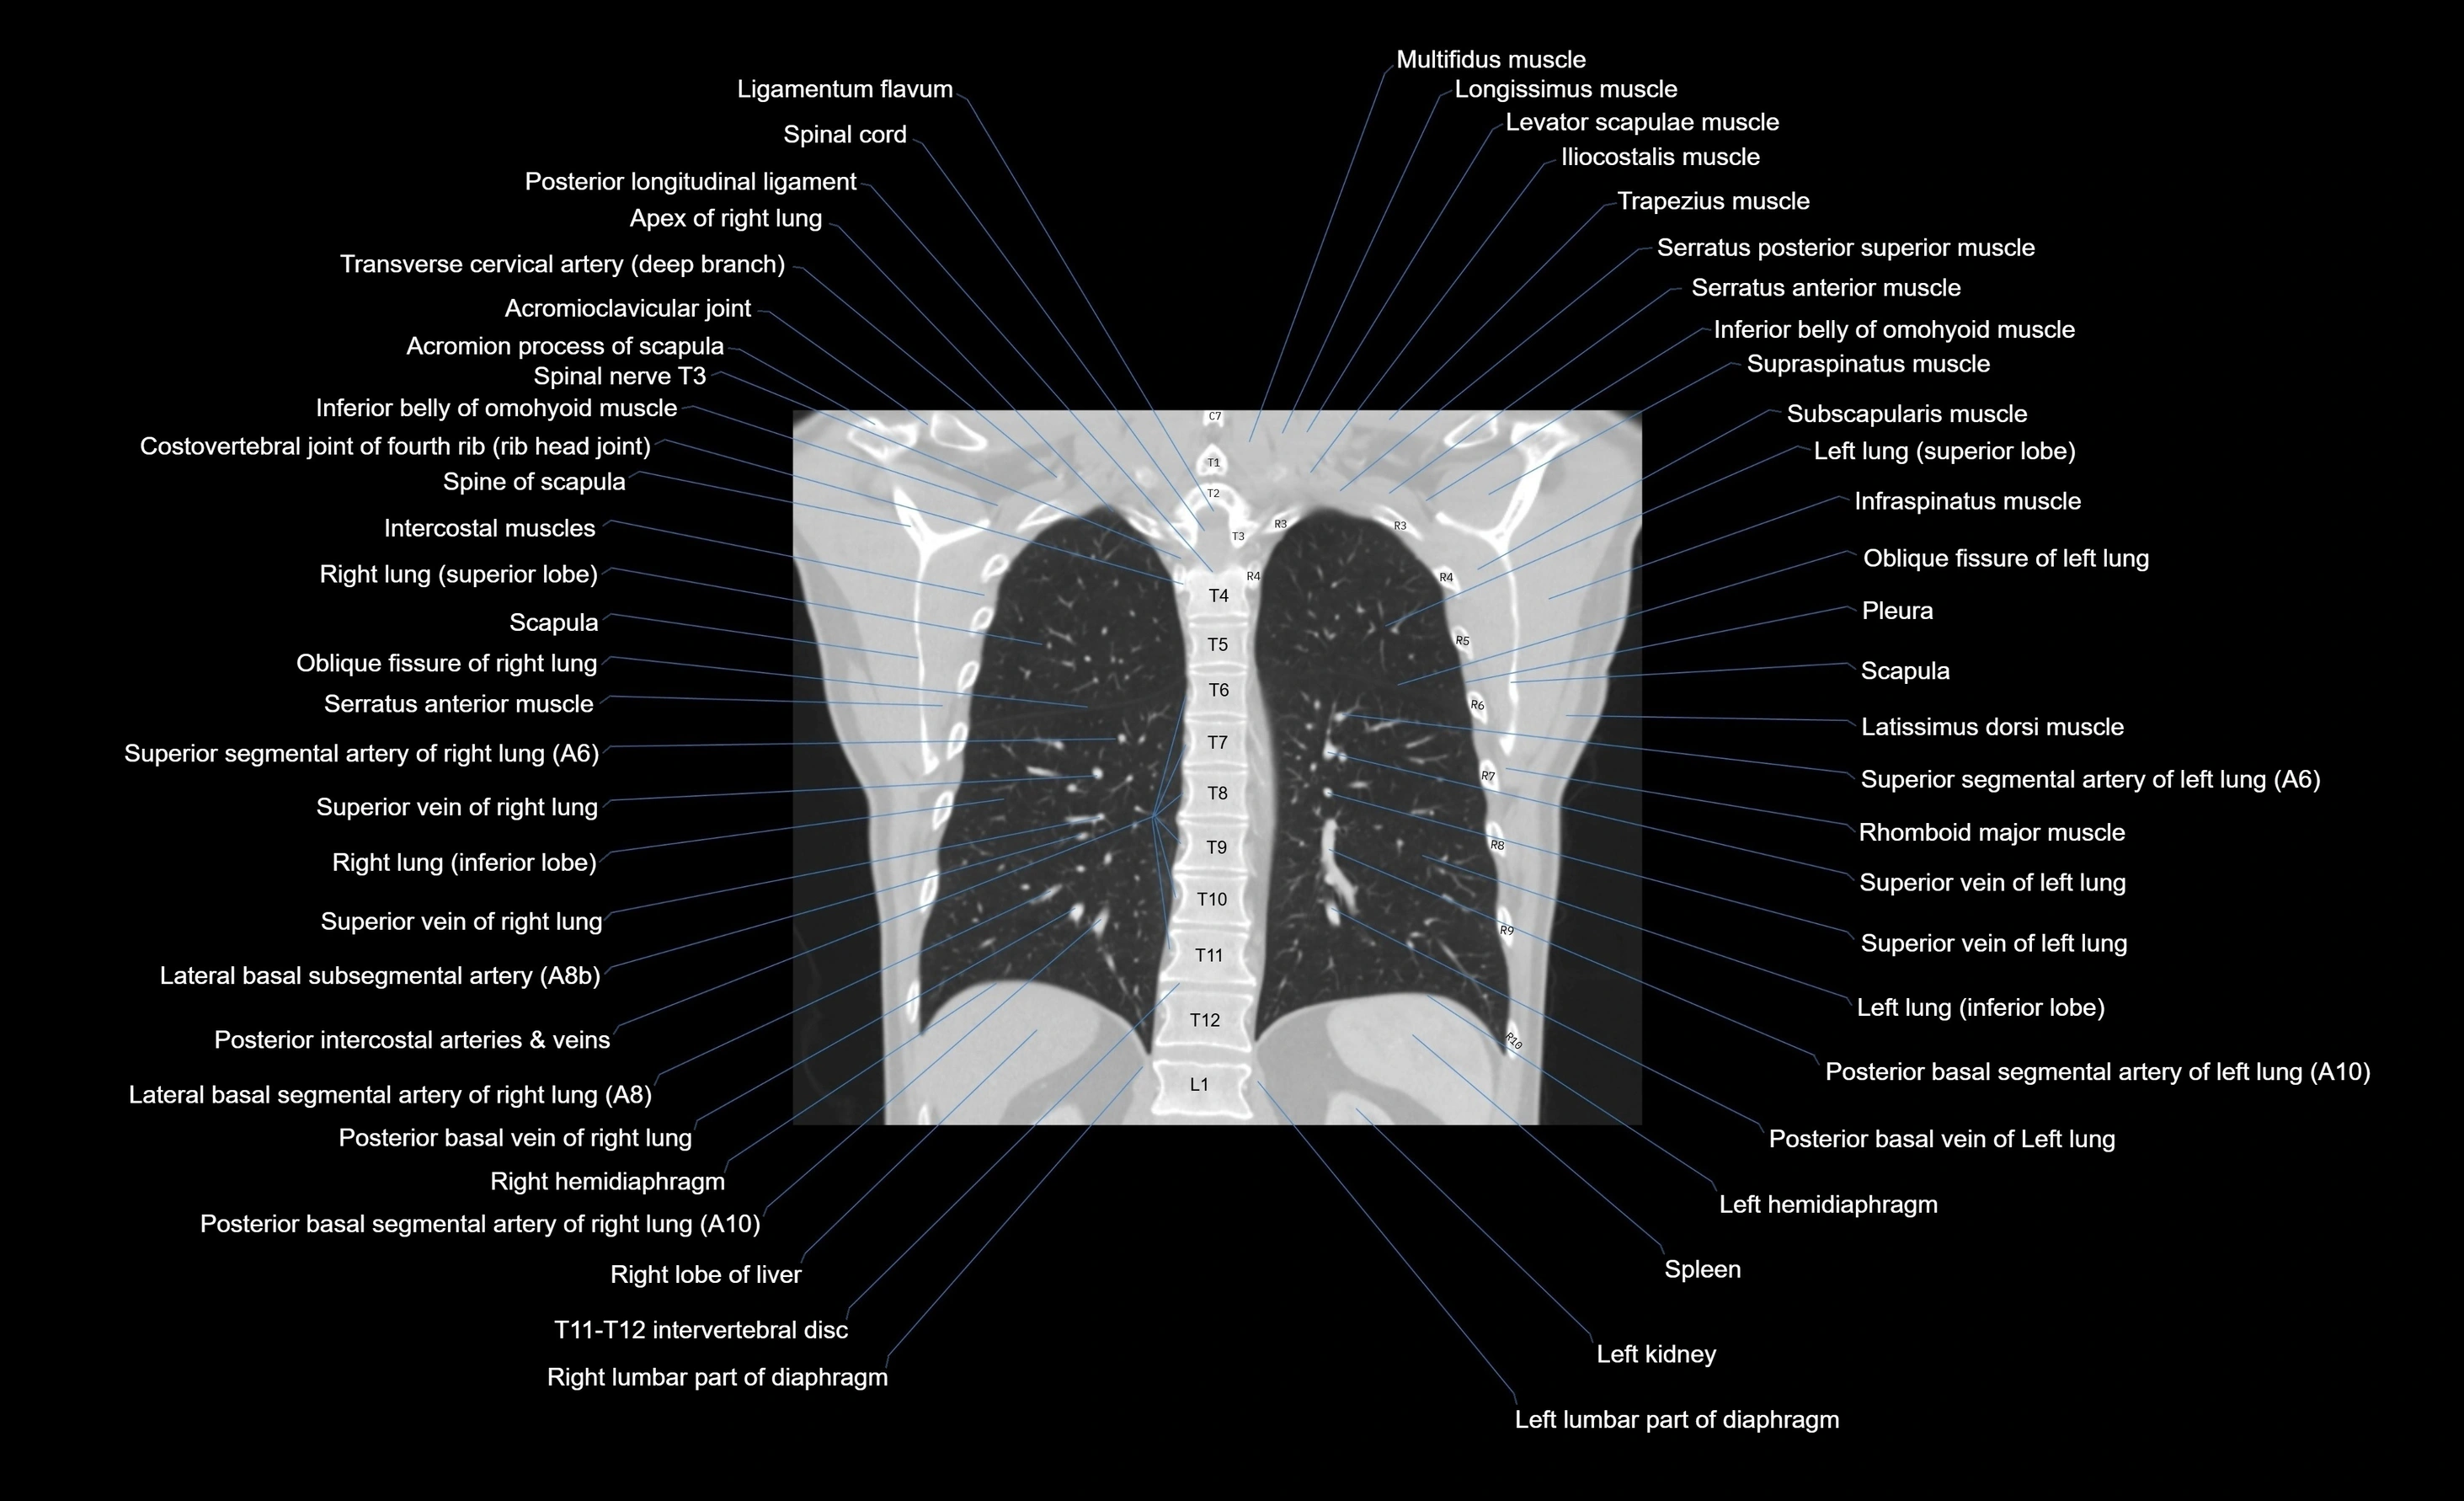

- T (Thoracic spine)

CT images